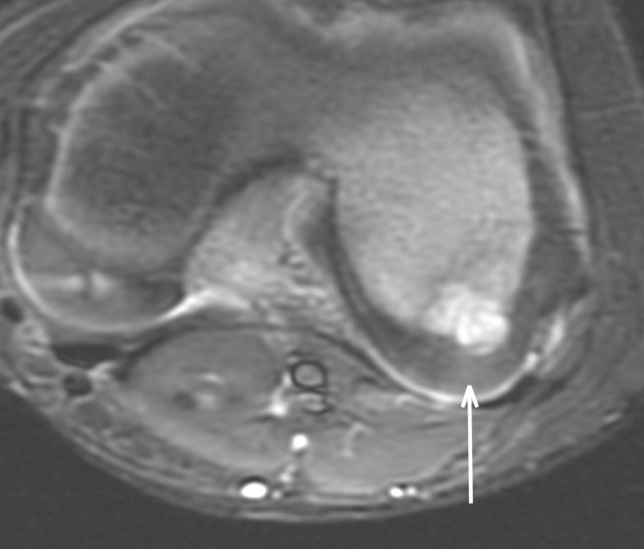

Figure 2 for case Staphylococcus osteomyelitis ( RID3715 )

Figure 2